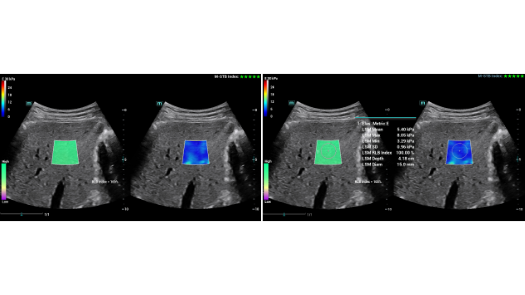

Dise?ado especĂficamente para usuarios de atenciĂłn primaria, el equipo Consona presenta soluciones nuevas y concretas que lo ayudan a realizar diagnĂłsticos sin problemas y de manera eficiente en diversos tipos de pacientes.

Independientemente de si lleva a cabo su rutina en hospitales o clĂnicas, o si estĂĄ perfeccionando sus habilidades en aplicaciones de diagnĂłstico por imĂĄgenes generales, atenciĂłn de la salud de la mujer o especialidades cardiovasculares, esta serie dispone de herramientas muy potentes para que se mantenga a la vanguardia.

GalerĂa de imĂĄgenes